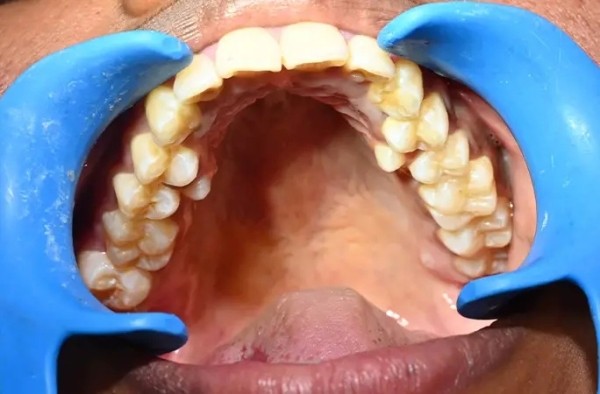

У девушки из Индии рекордное число зубов

У девушки на шесть зубов больше, чем у большинства людей: у жительницы Индии насчитали 38 зубов вместо 32-ух. При этом у неё нашли ещё два зуба, которые не прорезались. Больше только у мужчины из Канады — 41 штука.

По словам Калпаны, эти лишние зубы у нее с юности. Родители девушки рекомендовали ей удалить лишние зубы, однако она побоялась. Кроме того, дополнительные зубы не доставляли Калпане никакого неудобства, и она решила их сохранить.